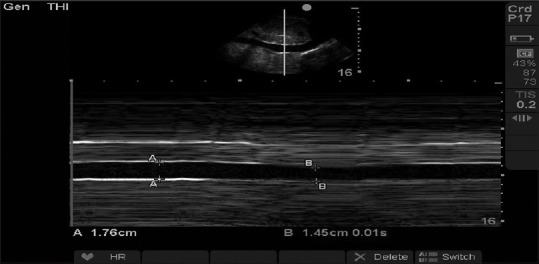

Objective: Fluid infusion, the most critical step in the resuscitation of patients with septic shock, needs preferably continuous invasive hemodynamic monitoring. The study was planned to evaluate the efficacy of ultrasonographically measured inferior vena cava collapsibility index (IVC CI) in comparison to central venous pressure (CVP) in predicting fluid responsiveness in septic shock.

Materials and methods: Thirty-six patients of septic shock requiring ventilatory support (invasive/noninvasive) were included. Patients with congestive heart failure, raised intra-abdominal pressure, and poor echo window were excluded from the study. They were randomly divided into two groups based on mode of fluid resuscitation - Group I (CVP) and Group II (IVC CI). Primary end-points were mean arterial pressure (MAP) of ≥65 mmHg and CVP >12 mmHg or IVC CI <20% in Groups I and II, respectively. Patients were followed till achievement of end-points or maximum of 6 h. Outcome variables (pulse rate, MAP, urine output, pH, base deficit, and ScvO2 ) were serially measured till the end of the study. Survival at 2 and 4 weeks was used as secondary end-point.

Results: Primary end-point was reached in 31 patients (15 in Group I and 16 in Group II). Fluid infusion, by either method, had increased CVP and decreased IVC CI with resultant negative correlation between them (Pearson correlation coefficient -0.626). There was no significant difference in the amount of fluid infused and time to reach end-point in two groups. Comparison in outcome variables at baseline and end-point showed no significant difference including mortality.

Conclusion: CVP and IVC CI are negatively correlated with fluid resuscitation, and both methods can be used for resuscitation, with IVC CI being noninferior to CVP.